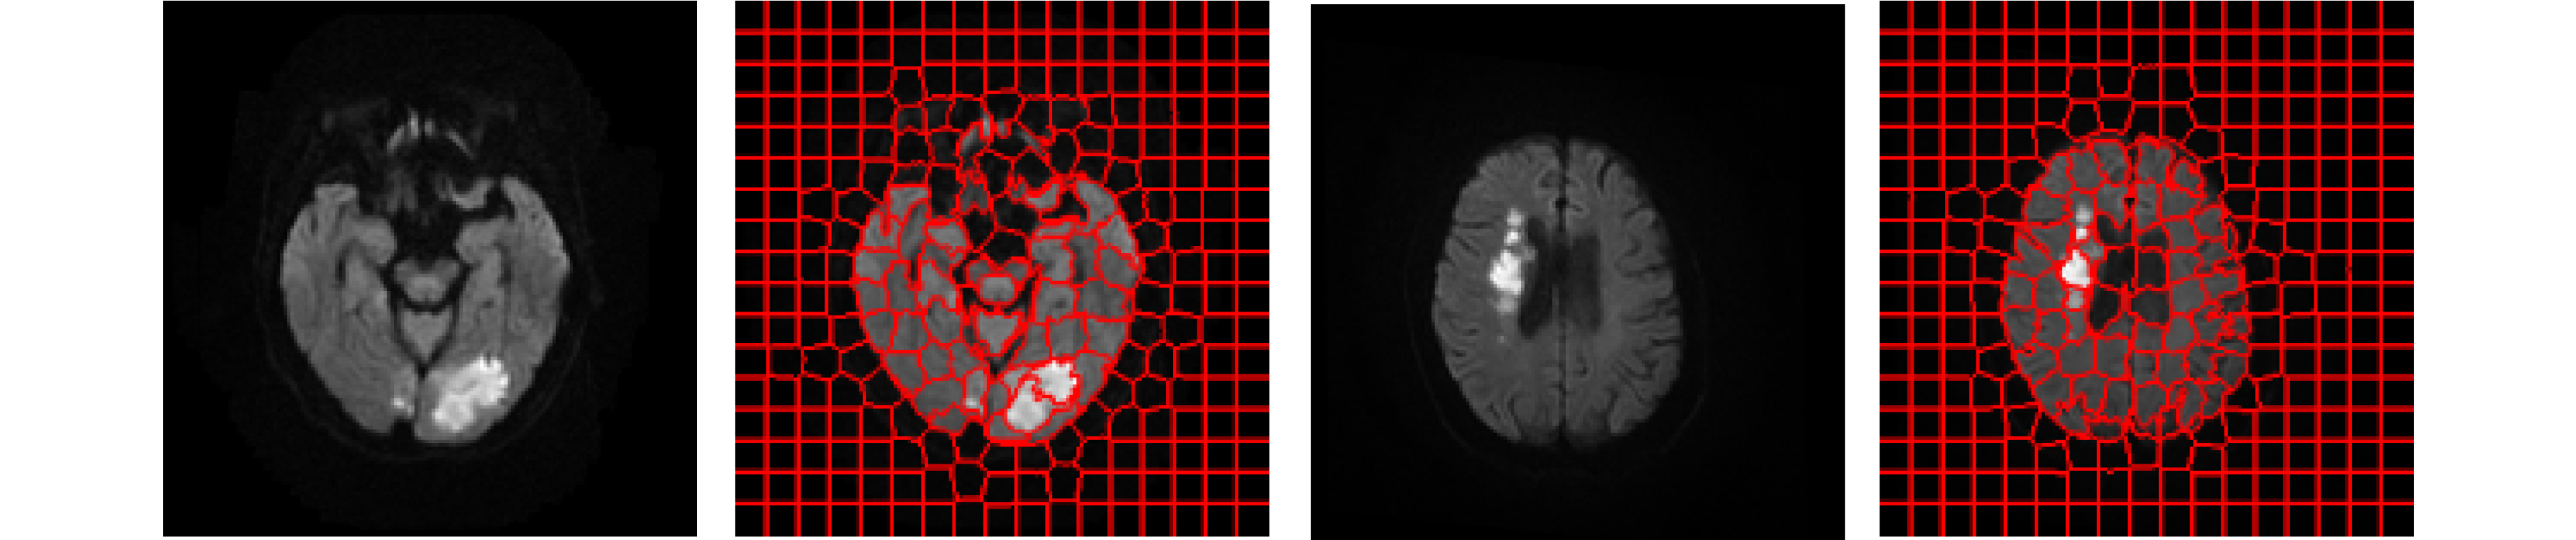

Objective In the clinical management of Acute Ischemic Stroke (AIS), Computed Tomography (CT) and Diffusion-Weighted Imaging (DWI) serve complementary roles at different stages. CT is widely applied for initial evaluation due to its rapid acquisition and accessibility, but it has limited sensitivity in detecting early ischemic changes, which can result in diagnostic uncertainty. In contrast, DWI demonstrates high sensitivity to early ischemic lesions, enabling visualization of diffusion-restricted regions soon after symptom onset. However, DWI acquisition requires a longer time, is susceptible to motion artifacts, and depends on scanner availability and patient cooperation, thereby reducing its clinical accessibility. The limited availability of multimodal imaging data remains a major challenge for timely and accurate AIS diagnosis. Therefore, developing a method capable of rapidly and accurately generating DWI images from CT scans has important clinical significance for improving diagnostic precision and guiding treatment planning. Existing medical image translation approaches primarily rely on statistical image features and overlook anatomical structures, which leads to blurred lesion regions and reduced structural fidelity. Methods This study proposes a Joint Mask and Multi-Frequency Dual Attention Generative Adversarial Network (JMMDA-GAN) for CT-to-DWI image synthesis to assist in the diagnosis and treatment of ischemic stroke. The approach incorporates anatomical priors from brain masks and adaptive multi-frequency feature fusion to improve image translation accuracy. JMMDA-GAN comprises three principal modules: a mask-guided feature fusion module, a multi-frequency attention encoder, and an adaptive fusion weighting module. The mask-guided feature fusion module integrates CT images with anatomical masks through convolution, embedding spatial priors to enhance feature representation and texture detail within brain regions and ischemic lesions. The multi-frequency attention encoder applies Discrete Wavelet Transform (DWT) to decompose images into low-frequency global components and high-frequency edge components. A dual-path attention mechanism facilitates cross-scale feature fusion, reducing high-frequency information loss and improving structural detail reconstruction. The adaptive fusion weighting module combines convolutional neural networks and attention mechanisms to dynamically learn the relative importance of input features. By assigning adaptive weights to multi-scale features, the module selectively enhances informative regions and suppresses redundant or noisy information. This process enables effective integration of low- and high-frequency features, thereby improving both global contextual consistency and local structural precision. Results and Discussions Extensive experiments were performed on two independent clinical datasets collected from different hospitals to assess the effectiveness of the proposed method. JMMDA-GAN achieved Mean Squared Error (MSE) values of 0.0097 and 0.0059 on Clinical Dataset 1 and Clinical Dataset 2, respectively, exceeding state-of-the-art models by reducing MSE by 35.8% and 35.2% compared with ARGAN. The proposed network reached peak Signal-to-Noise Ratio (PSNR) values of 26.75 dB and 28.12 dB, showing improvements of 30.7% and 7.9% over the best existing methods. For Structural Similarity Index (SSIM), JMMDA-GAN achieved 0.753 and 0.844, indicating superior structural preservation and perceptual quality. Visual analysis further demonstrates that JMMDA-GAN restores lesion morphology and fine texture features with higher fidelity, producing sharper lesion boundaries and improved structural consistency compared with other methods. Cross-center generalization and multi-center mixed experiments confirm that the model maintains stable performance across institutions, highlighting its robustness and adaptability in clinical settings. Parameter sensitivity analysis shows that the combination of Haar wavelet and four attention heads achieves an optimal balance between global structural retention and local detail reconstruction. Moreover, superpixel-based gray-level correlation experiments demonstrate that JMMDA-GAN exceeds existing models in both local consistency and global image quality, confirming its capacity to generate realistic and diagnostically reliable DWI images from CT inputs. Conclusions This study proposes a novel JMMDA-GAN designed to enhance lesion and texture detail generation by incorporating anatomical structural information. The method achieves this through three principal modules. (1) The mask-guided feature fusion module effectively integrates anatomical structure information, with particular optimization of the lesion region. The mask-guided network focuses on critical lesion features, ensuring accurate restoration of lesion morphology and boundaries. By combining mask and image data, the method preserves the overall anatomical structure while enhancing lesion areas, preventing boundary blurring and texture loss commonly observed in traditional approaches, thereby improving diagnostic reliability. (2) The multi-frequency feature fusion module jointly optimizes low- and high-frequency features to enhance image detail. This integration preserves global structural integrity while refining local features, producing visually realistic and high-fidelity images. (3) The adaptive fusion weighting module dynamically adjusts the learning strategy for frequency-domain features according to image content, enabling the network to manage texture variations and complex anatomical structures effectively, thereby improving overall image quality. Through the coordinated function of these modules, the proposed method enhances image realism and diagnostic precision. Experimental results demonstrate that JMMDA-GAN exceeds existing advanced models across multiple clinical datasets, highlighting its potential to support clinicians in the diagnosis and management of AIS. -